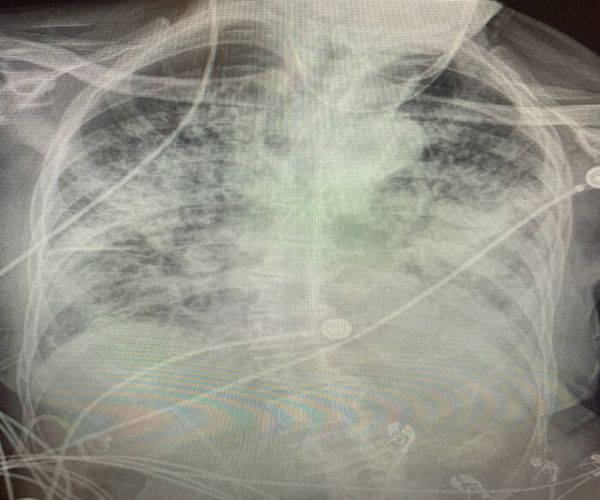

kovid

Третата слика ги прикажува белите дробови на пациент кој боледувал од Ковид-19. Може да се забележи дека снимката е речиси бела, што значи дека белите дробови се сериозно оштетни.